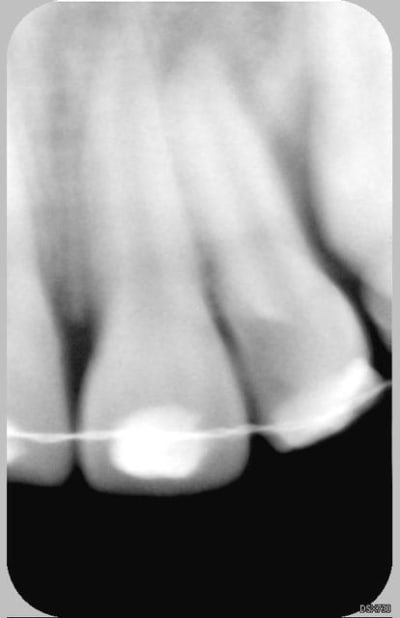

Patiente de 11 ans ayant la 21 expulsée début avril 2006. La dent a été repositionnée en centre de soins. Dans un premier temps, pas de perte de sensibilité. Puis dans un deuxième temps, comme un goût de ça tourne mal avec certainement rhyzalyse interne de la 22 (traitement thermafil pas d'école).

la on est dans un tres beau cas de resorption inflammatoire des 21 et 22

pour la 21,ne pas toucher au fantome de racine qui reste,il va disparaitre

Ci joint la première radio de ces dents avec attelles centre de soins universitaire